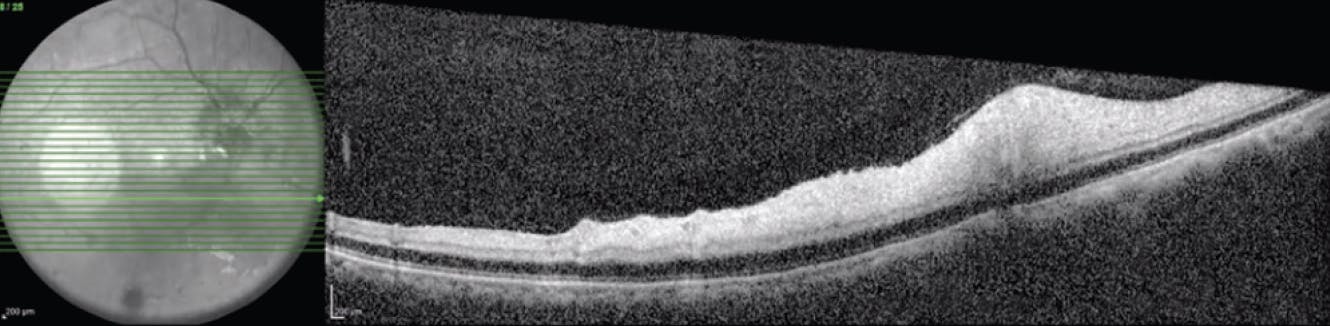

Fluorescein angiography revealed hypofluorescence due to the absence of filling of the vascular prepapillary loop and inferior temporal artery (Figure 3). Macular OCT showed hyperreflectivity of the internal retinal layers in the area of the inferior macula due to edema secondary to ischemia (Figure 4).

<p>Figure 4. OCT showed hyperreflectivity of the internal layers in the area of the inferior macula due to edema secondary to ischemia that does not allow for delimitation of the cellular layers.</p>

Figure 4. OCT showed hyperreflectivity of the internal layers in the area of the inferior macula due to edema secondary to ischemia that does not allow for delimitation of the cellular layers.